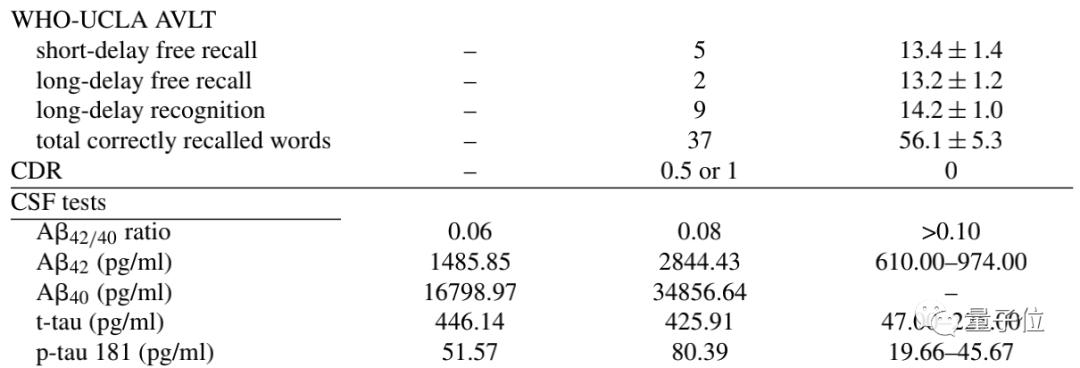

尽管这两项得分还算说得过去,但在关于记忆力(没错,又是记忆)的测试“WHO-UCLA AVLT”上,问题就显现出来了。

记忆力这块共包括4项:

即时回忆、短延迟自由回忆(3分钟后)、长延迟自由回忆(30分钟后),以及长延迟识别。

可惜男孩在这4种记忆测试中,结果全都低于正常值。其中,“长延迟自由回忆能力”的衰退尤为严重,正常人能正确回忆起13.2 ± 1.2个单词,但他只能想起2个。

另外,他们还检查了男孩的脑脊液,结果显示:p-tau181蛋白浓度增加,淀粉样蛋白-β 42/40比例降。